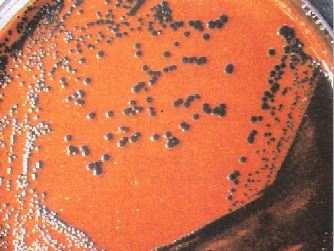

محامي وصل منذ ثلاثة أيام من السفر أحضر إلى قسم الطوارئ وهو يعاني من تقرح الحلق sore throat و orodynia ، صداع مع فشل عام، كما يعاني من ارتفاع في درجة الحرارة ونوبات تسرع ضربات القلم tachycardia . بفحص البلعوم لوحظ وجود غشاء ملتصق على الحلقوم. اخذت مسحة وأرسلت إلى مختبر التحليل الجرثومي لفحصها مجهرياً كما في الشكل رقم 1 وزراعتها على وسط غذائي مناسب كما في الشكل رقم 2 . تم إجراء الاختبار المعملي كما في الشكل رقم 3 .

الشكل رقم 1 : الفحص المجهري

2- يتم التاكد من التشخيص بأخذ مسحة من الحلق والأنف لفحصها مجهرياً وزراعتها على الوسط الغذائي المناسب وهو الوسط الغذائي Hoyle's أو الوسط الغذائي Tindsale's medium وهما وسط غذائي انتقائي وتفريقي.